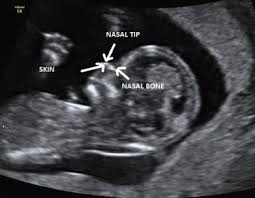

Three Dimensional Ultrasound With Maximal Mode Rendering A Novel Technique For The Diagnosis Of Bilateral Or Unilateral Absence Or Hypoplasia Of Nasal Bones In Second Trimester Screening For Down Syndrome Benoit 2005

Short Nasal Bone

Fetal Nasal Bone Hypoplasia In The Second Trimester And Risk Of Abnormal Karyotype In A Population